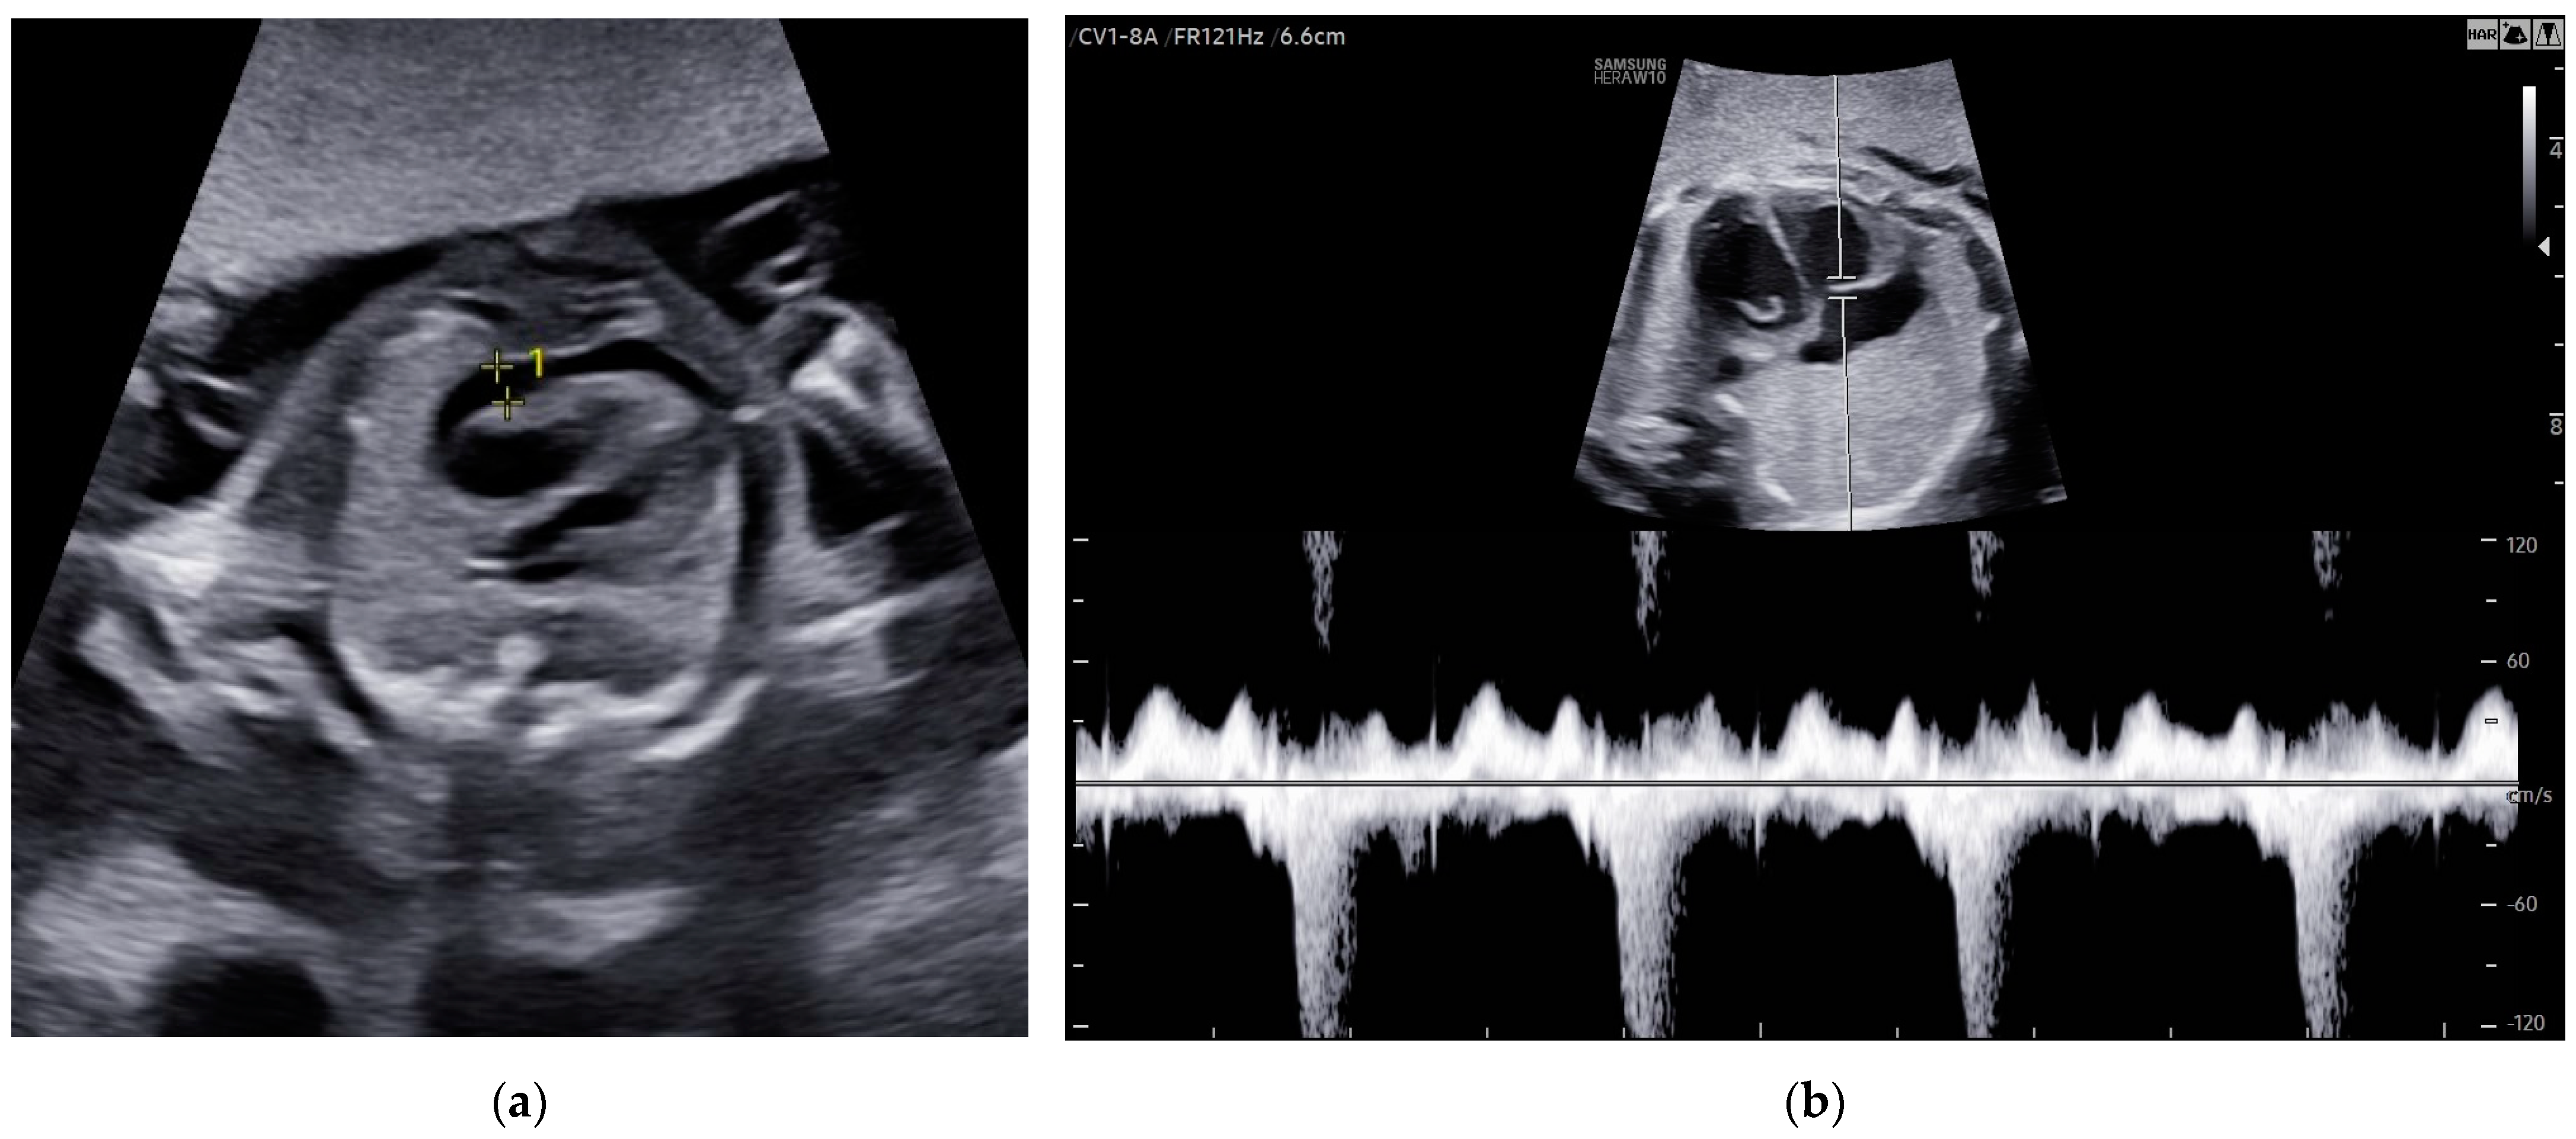

A 29-year-old woman, in the 21st week of her second pregnancy, was referred to the hospital due to anomalies detected during the anatomy scan—specifically, fetal hydrops accompanied by ascites and pericardial effusion (Figure 7a).

Three weeks after the last intrauterine transfusion, the patient underwent a follow-up ultrasound examination, revealing almost complete resolution of fetal hydrops, with only a small amount of fluid remaining in the pericardium. Fetal echocardiography detected mitral valve regurgitation (Figure 7b). The PSV of the MCA measured 47.57 cm/s (1.37 MoM), which was within normal limits. The estimated fetal weight was 920 g, appropriate for the gestational age.

Figure 7. Case 7: Abnormalities in the fetal heart ultrasound: (a) pericardial effusion before the first intrauterine transfusion, 21 weeks of gestation; (b) regurgitation of the mitral valve and total resolution of pericardial effusion, 2 weeks after the second intrauterine transfusion.